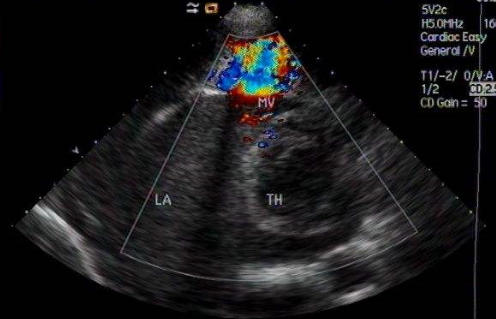

(2)超聲心動(dòng)圖

是確診二尖瓣狹窄首選無創(chuàng)性檢查,可直接觀察瓣葉活動(dòng)、測量瓣口面積、房室腔大小及左房內(nèi)血栓,或測算血流速度、跨瓣壓差及瓣口面積。是確診本病和評估病情的精確方法。

?、诙S超聲

舒張期瓣葉開放受跟,前葉呈圓窿狀,后葉活動(dòng)差;短軸圖可見瓣口縮小,開放呈魚嘴狀,可直接測量瓣口解剖面積。

③多普勒

測算血流速度、跨瓣壓差(包括肺動(dòng)脈壓)及瓣口面積。